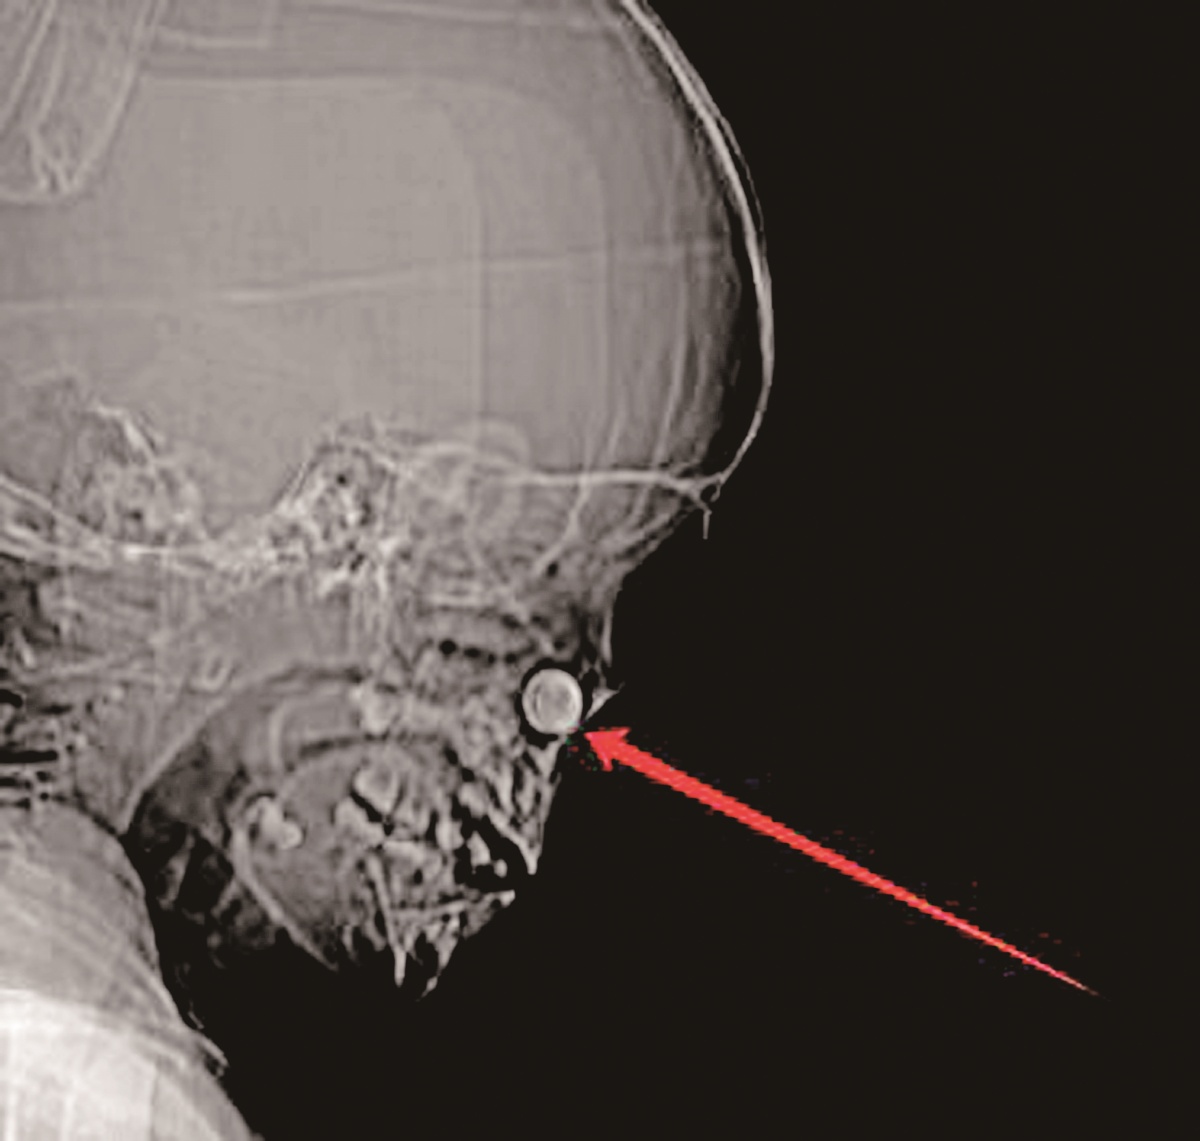

ct影像图显示,患儿鼻腔内有一圆形异物.

图片尺寸1200x1141